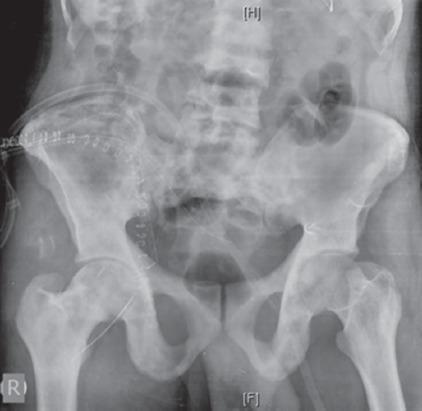

一名 40 岁男性因背痛就诊,经评估诊断为多骨型 PDB。他接受了静脉注射双膦酸盐、钙剂和维生素 D 补充剂治疗。在无症状的 3 年后,他出现了累及髂骨和骶骨的臀肌肿块,活检确诊为 GCT。尝试了系列血管栓塞术,但肿块仍进展,因此进行了手术,切除并刮除病变。2 年后他出现局部复发,伴有大量软组织成分。开始使用地诺单抗(一种 RANKL 抑制剂),目的是降低病变分期。患者在 6 次给药后显示出良好反应,软组织肿块缩小,随后接受了部分 T-1 型内部半骨盆切除术和骶骨刮除术。目前,患者在 15 个月的随访中无症状。

结论

GCT-PDB 是一种罕见现象,主要发生在多骨型 PDB 中,且与该疾病更严重的表现相关。其治疗具有挑战性,需要多模式管理。药物治疗包括使用双膦酸盐和 RANK 配体抑制剂——地诺单抗。虽然手术是 GCT 的主要治疗方法,但对于无法手术的病例或手术会导致功能严重受损的情况,尤其是在 GCT-PDB 中疾病更常累及中轴骨骼的病例,必须使用其他治疗方式,如 RANK 配体抑制剂(地诺单抗)、选择性动脉栓塞或放射治疗。